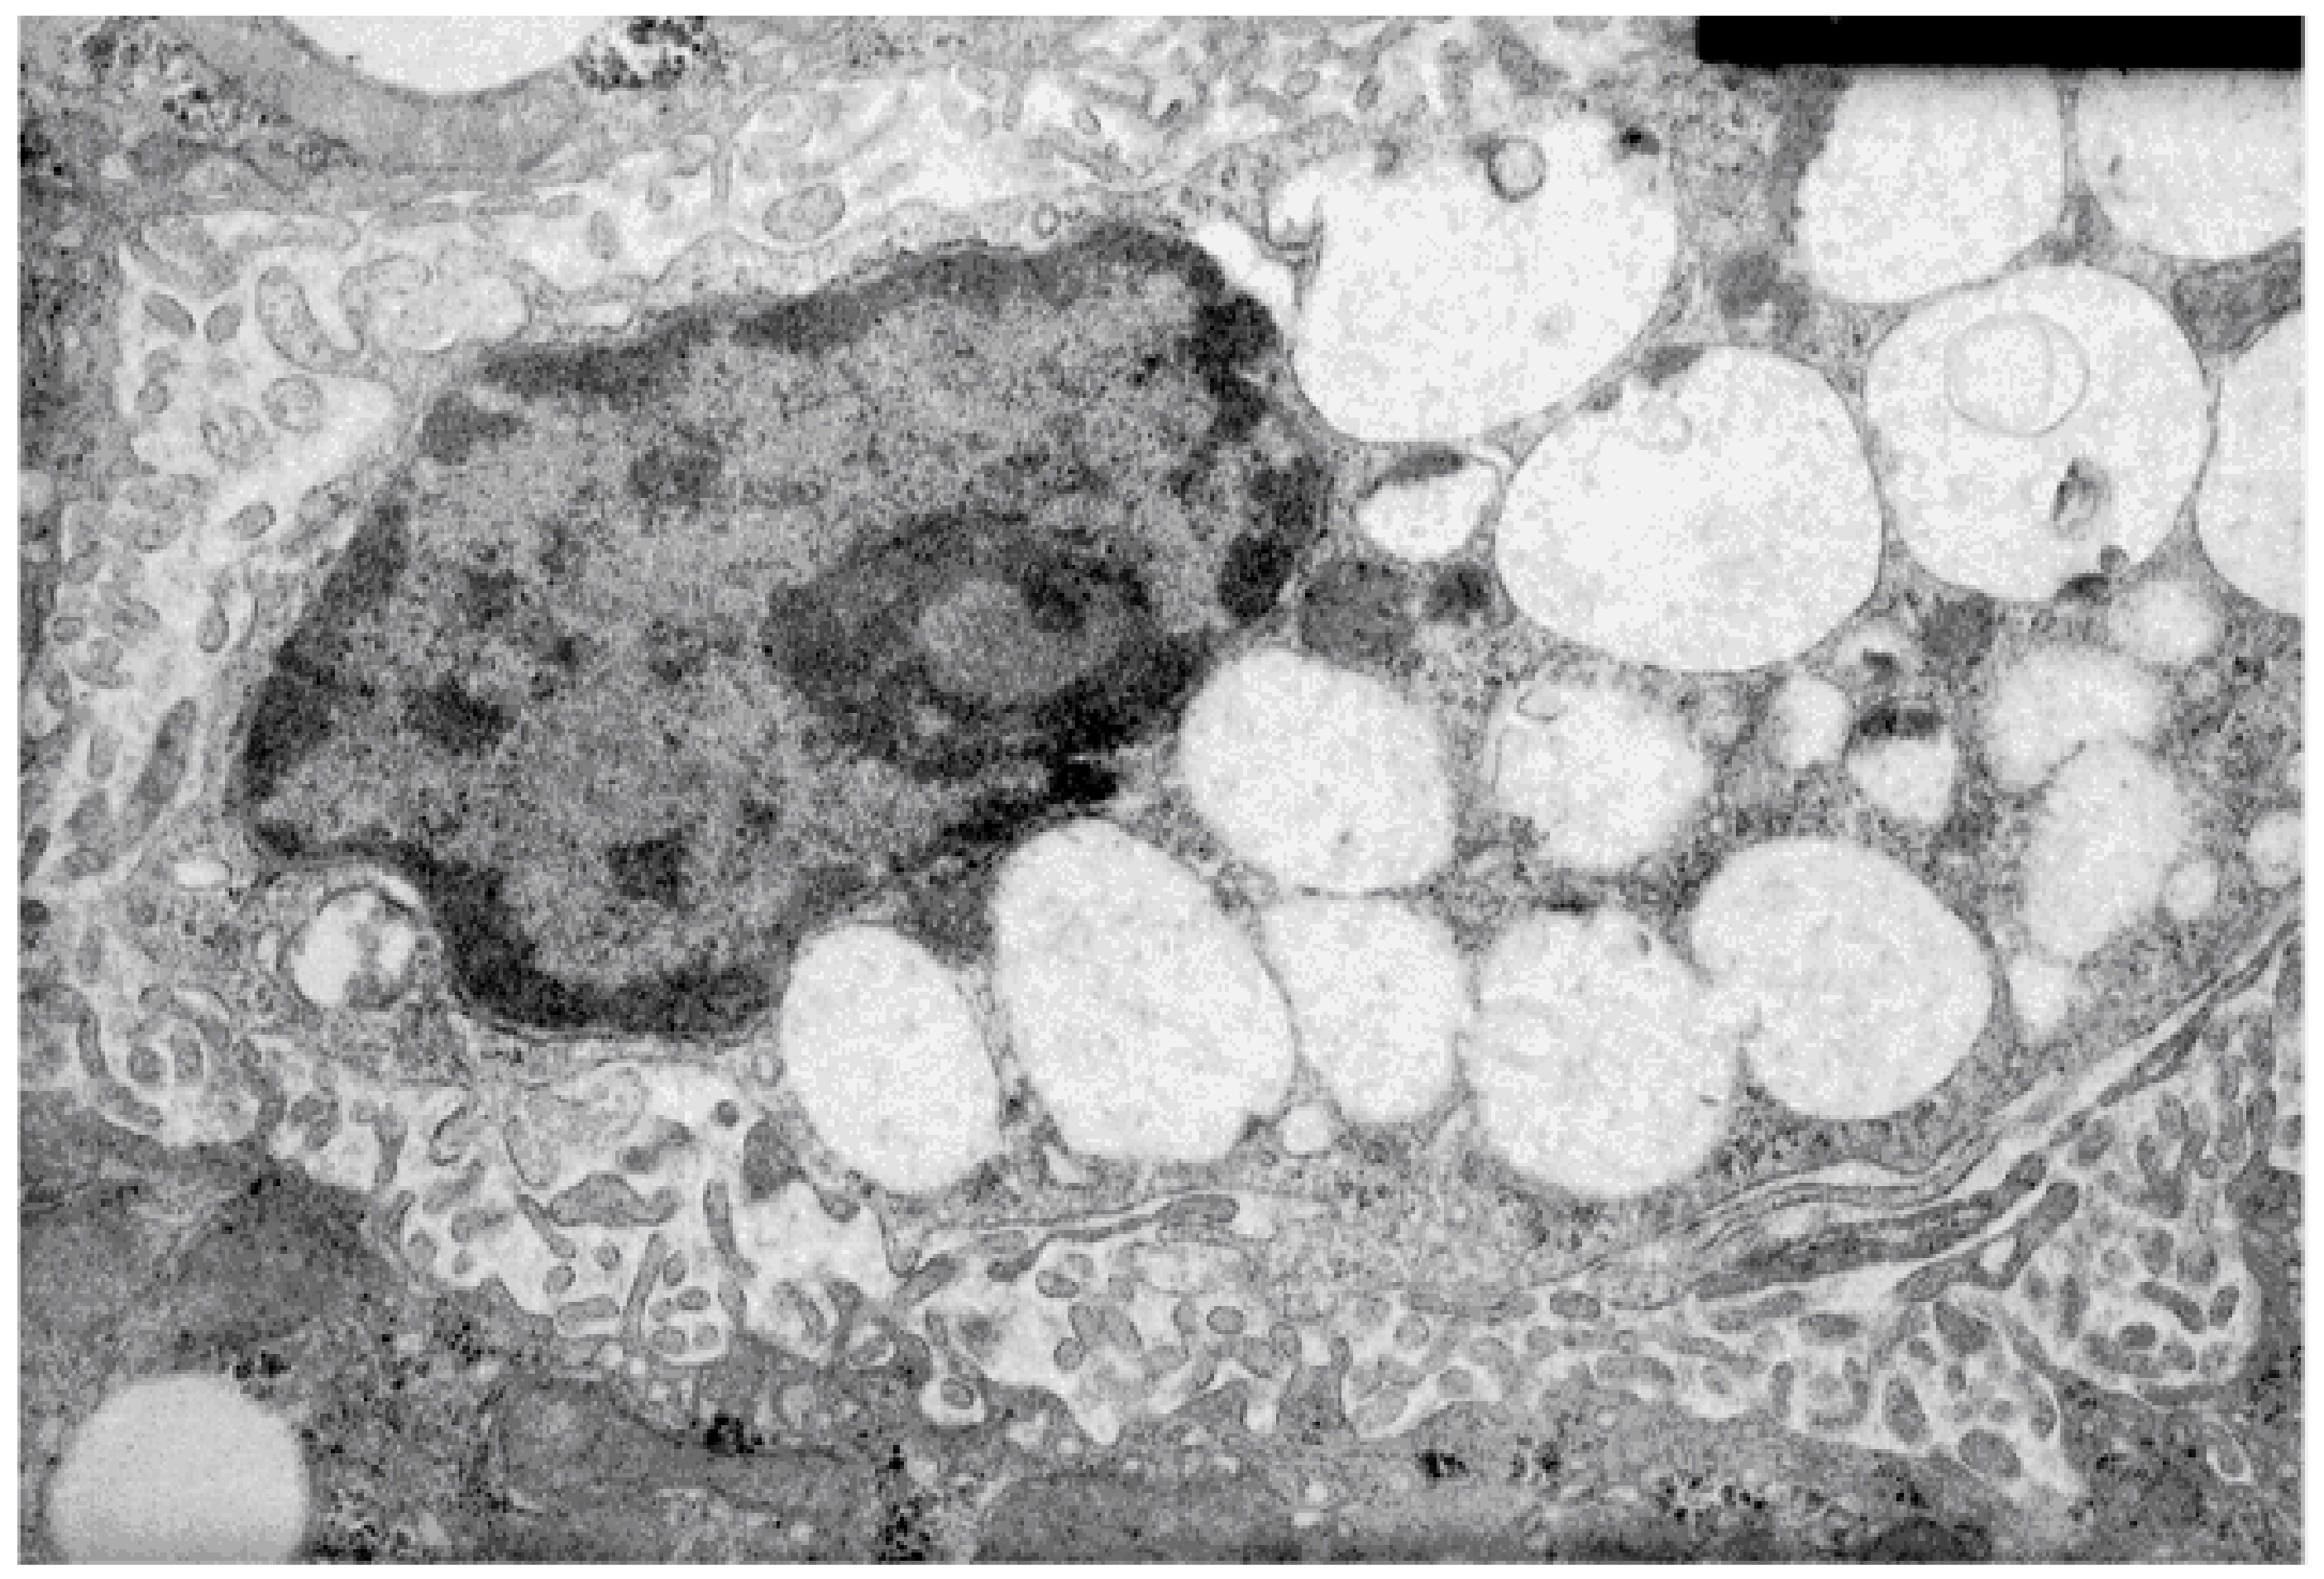

In vivo, Triton WR 1339 influences liver macrophages, forming numerous so-called triton-filled lysosomes (Figure 2). However, in vitro, Triton WR 1339 exposure manifests dose- and time-dependent cytotoxicity. Triton WR 1339 treatment damages RAW 264.7 cells more than NIH/3T3 cells. All of the cells exposed to Triton WR 1339 show some morphological features of apoptosis, such as chromatin condensation and cell shrinkage [115].

Figure 2.

An electron micrograph of a murine liver macrophage after single intraperitoneal administration of lysosomotropic agent (LA) Triton WR 1339 (500 mg/kg, 4 days after); droplets containing lipids are seen in the cytoplasm.